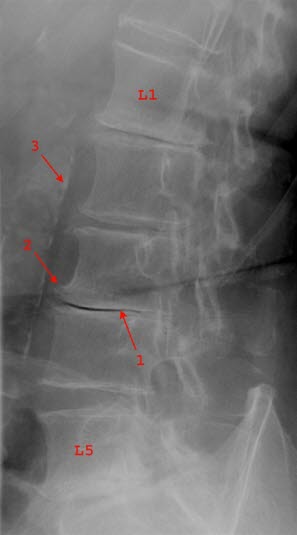

Diagnosen stilles ved hjelp av vanlige røntgenbilder av ryggraden. Man kan i mange tilfeller se at noen av mellomvirvelskivene er smalere enn normalt. Ofte kan en også se forkalkninger i ryggvirvlene eller i leddbåndene.

Spondylose er svært ofte et tilfeldig funn hos ellers friske individer. MR-undersøkelser av personer uten symptomer viser at cirka 50 prosent av personer over 40 år, har slitasjeforandringer i mellomvirvelskivene i brystdelen av ryggsøylen. Det er derfor liten sammenheng mellom røntgenfunn og grad av plager. I noen tilfeller med svære forandringer på bildene kan plagene være beskjedne, i andre tilfeller er plagene uttalte med beskjedne forandringer på røntgen.